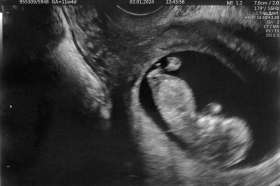

Tomášek - ještě v bříšku

2023-09-26